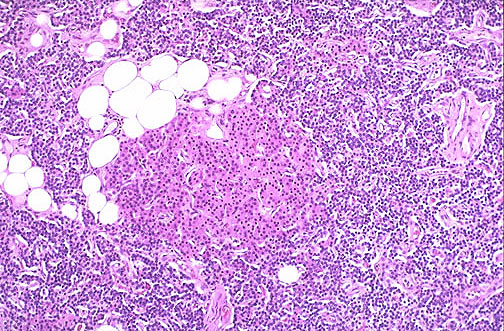

![]() | In parathyroid hyperplasia, there is little or no adipose tissue, but any or all cell types normally found in a parathyroid gland are present. Note the pink oxyphil cells in the nodule seen here. This is actually "secondary hyperparathyroidism" with enlarged glands as a consequence of chronic renal failure with impaired phosphate excretion. The increased serum phosphate tends to drive serum calcium down, which in turn drives the parathyroids to secrete more parathormone. |